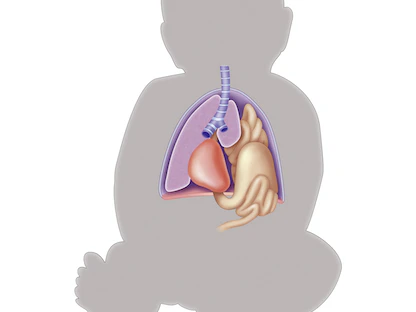

يحدث الفتق الحجابي عندما يبرز الجزء العلوي من المعدة عابراً من العضلة الكبيرة التي تفصل البطن عن الصدر، وهي العضلة المسماة بالحجاب الحاجز.

توجد في الحجاب الحاجز فتحة صغيرة تسمى الفُرجة الحِجابية. ويمر الأنبوب الذي تبتلع به الطعام -الذي يُطلَق عليه المريء- عبر الفُرجة الحِجابية قبل أن يتصل بالمعدة. وفي الإصابة بالفتق الحجابي، تبرز المعدة من خلال تلك الفتحة باتجاه الصدر.